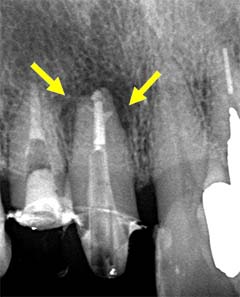

この複雑さは、レントゲンの2D画像だけでは把握できず、肉眼での治療はまさに「懐中電灯なしで洞窟を探検するようなもの」。根管治療が失敗しやすい理由は、見えないものを手探りで治す構造的限界にあります。

当院での治療例です。ご来院された(初診時)治療前の状態と根充後(治療後)の状態をレントゲンとCTで確認すると次のようになります。

しっかりと根充されていることがCTにより確認すことができます。